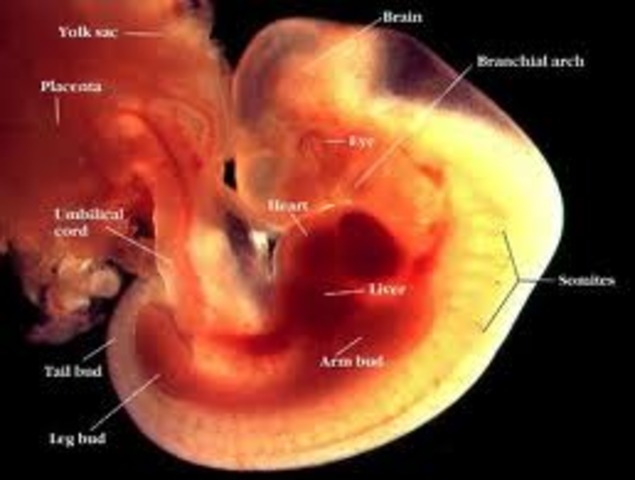

week 5

Your baby now resembles a teeny tadpole (complete with a tiny tail) and is about the size of an orange seed. The circulatory (or blood) system, along with the heart, is the first part of that tiny body to be functional; and as your baby's heart starts to form, you may even be able to see it beating on an early ultrasound. Another part of your little tadpole that is under construction: the neural tube, which will eventually become your baby's brain and spinal cord.